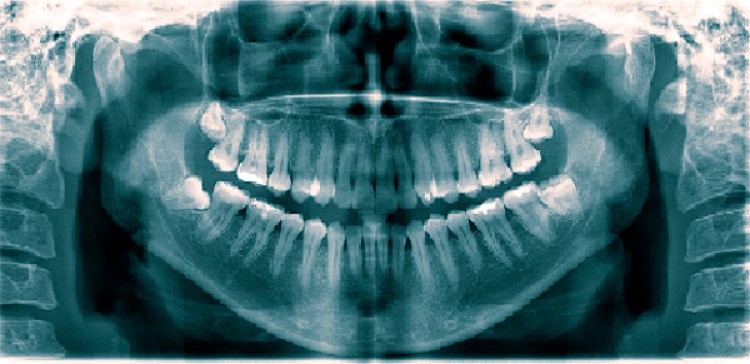

Radiografía panorámica en la práctica odontológica: conocida también como ortopantomografía, la panorámica dental es una radiografía digital que ofrece una imagen general y clara tanto de las piezas dentarias como de los maxilares. Por tratarse de una toma general de esta zona, que se plasma en una única radiografía, este estudio resulta de gran utilidad para el diagnóstico en diversas ramas de la odontología.El uso de la radiografía panorámica se ha incrementado en la práctica privada, en los hospitales y dentro de los servicios odontológicos. Proporciona un examen sistemático en niños, adultos y en pacientes desdentados, también es de gran valor para realizar la evaluación pre y post tratamiento. La calidad diagnóstica de la imagen en la radiografía panorámica depende de brindar especial atención en la realización de una correcta técnica y procesado. Es una técnica que tiene alcances y limitaciones que deben ser consideradas por el profesional para no incurrir en errores diagnósticos. Una radiografía panorámica dental aporta información por demás valiosa a la hora de realizar un diagnóstico, razón por la cual en la actualidad se ha convertido en un estudio que se efectúa de modo rutinario, brindando una ayuda esencial a los odontólogos. Disciplinas como la implantología, la ortodoncia, la cirugía bucal y la periodoncia se benefician cotidianamente de los detalles que brindan estas imágenes digitales generales; y en lo que refiere a la determinación de patologías dentales y orales. La radiografía panorámica es responsable por el hallazgo e identificación de un 40% de patologías, tanto principales como secundarias. Comparada con las radiografías periapicales (otra técnica usada a la hora de efectuar radiografías intrabucales), en el diagnóstico la radiografía dental panorámica permite ampliar el campo en aproximadamente un 70%, reduciendo a la vez la radiación a la que se somete el paciente en un 90%.